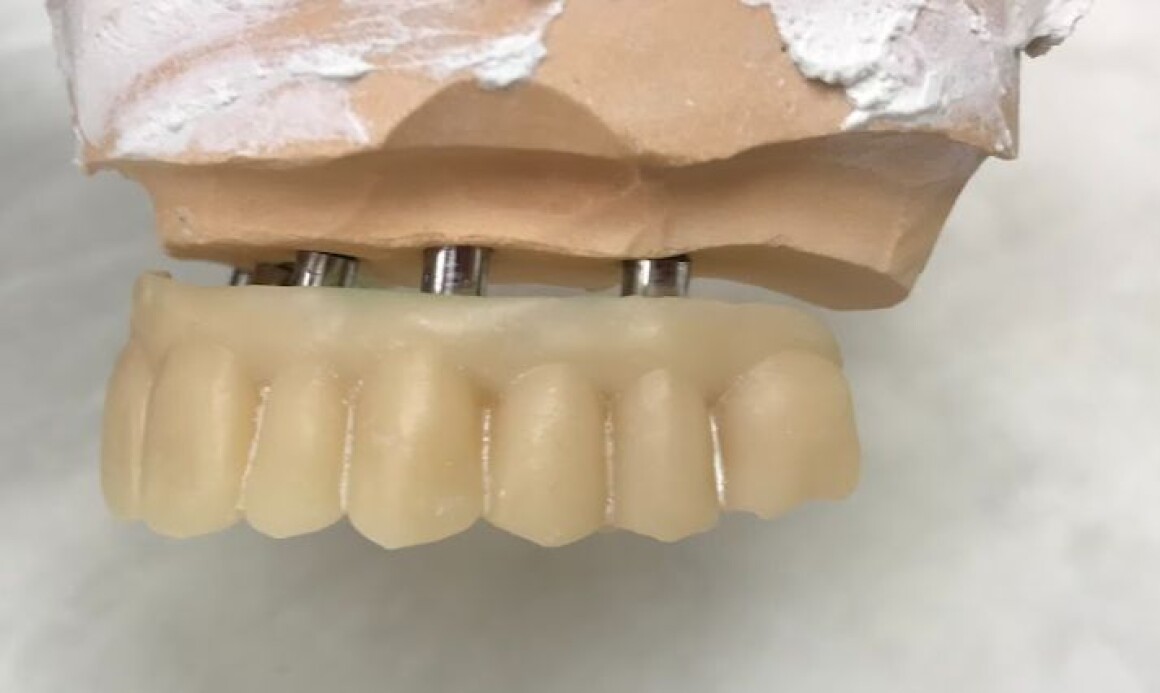

Тотальная реабилитация

• Изготовление временных конструкций на имплантантах

• Установка временных коронок на имплантантах

• Установка постоянной конструкции из металлокерамики верх и низ